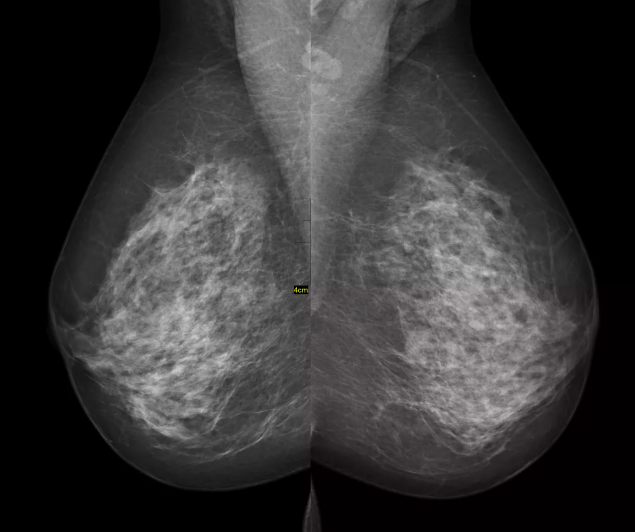

Gli screening mammografici sono stati oggetto di dibattito per decenni: pur essendo tra i più studiati, sono tra quelli che ancora destano maggiori polemiche; questo dovrebbe aiutare a capire quanto sia delicato il bilanciamento tra rischi e benefici. In più, è un argomento spinoso di cui trattare: quando si parla di lotta contro il cancro, ci sentiamo parte di una guerra contro un nemico da combattere con ogni arma possibile, senza esclusione di colpi. Aver vissuto la malattia al fianco di amici o parenti, aver condiviso le loro sofferenze e paure ci porta a pensare che qualunque rischio sia accettabile, pur di scongiurare l’eventualità di incontrare “L’imperatore del male”, come l’ha definito Siddhartha Mukherjee. Secondo uno studio di fine 2017, pubblicato su Jama (Journal of American Medical Association – la rivista della società statunitense di medicina) Internal Medicine, questo può influenzare anche i medici: se una parente, un’amica, una paziente o la dottoressa stessa hanno ricevuto una diagnosi tardiva, tendono a prescrivere una mammografia anche alle donne che non rientrano nelle linee guida per le quali viene consigliata.

Ma come nascono queste linee guida, e c’è comune accordo su di esse? Il primo studio randomizzato iniziò nel 1963 negli Stati Uniti e coinvolse circa 62 000 donne. Di queste, una parte riceveva un esame clinico del seno e una mammografia, l’altro non solo non riceveva nulla, ma non era nemmeno consapevole di far parte di una simile ricerca. Si può comprendere abbastanza facilmente il limite di un’indagine effettuata in questo modo: non permette di individuare i benefici delle mammografie rispetto all’esame clinico e a una maggior consapevolezza sull’importanza di un trattamento precoce del tumore al seno. In ogni caso, dopo 10 anni di indagine, nel gruppo sul quale si era effettuata una diagnostica preventiva le donne con 50 anni o più avevano una probabilità del 30% in meno di morire per un cancro alla mammella, mentre non si osservò nessuna riduzione tra le donne di 40 o più.

Nel 1973 l’American Cancer Society e l’Istituto Nazionale Tumori diedero inizio a un programma nazionale di screening, invitando tutte le donne sopra i 35 anni a sottoporvisi, malgrado non vi fossero prove scientifiche che ne avrebbero beneficiato anche in giovane età. Nel 1976, infatti, le due organizzazioni esclusero le donne sotto i 50 anni, a causa dei rischi che un simile accumulo di radiazioni – dovuto a mammografi meno efficienti di quelli di oggi e alla giovane età delle pazienti, che quindi ne avrebbero effettuate molte di più nel corso della vita – avrebbero avuto su un organo sensibile come la mammella. Nel 1988 cambiarono di nuovo le indicazioni: ora lo screening avrebbe riguardato chi aveva più di 40 anni, visto che i nuovi macchinari emettevano meno radiazioni. Ma non era una scelta destinata a durare: nel 1992 i risultati di un nuovo grande studio randomizzato canadese, focalizzato sulle donne tra i 40 e i 49 anni, mostravano che lo screening non riduceva il numero di decessi per questo tipo di cancro.

Anche la questione delle 270 vite abbreviate è abbastanza fuorviante, secondo David Spiegelhalter, statistico e Presidente del Winton Centre for Risk and Evidence Communication alla Cambridge University. “C’è solo una scarsa evidenza che lo screening mammografico aiuti ad allungare la vita, soprattutto per le donne più anziane e contrariamente a quanto si crede, lo screening può anche fare male”. Questo a causa dei rischi che presenta, dei quali non sempre vengono informate le donne. Per incoraggiarne sempre più a sottoporvisi, si cerca di renderle più consapevoli, e purtroppo la strategia più efficace sembra essere quella di intimorirle, rendendo la popolazione più ansiosa. Il test in sé, da molte definito accettabile, da altre viene vissuto come spiacevole, o addirittura doloroso. Cosa accade, poi, quando si individua un’anomalia? In America si stima che circa la metà delle donne, nell’arco di 10 anni di controlli annuali, si senta dire che c’è qualcosa che non va. A quel punto può essere richiesto di ripetere immediatamente l’esame, o di ripresentarsi dopo 6 mesi, o di fare una biopsia. Tutte vivranno la preoccupazione di avere un tumore al seno, anche se la maggioranza non ne ha uno. È il caso dei falsi positivi. Se invece il cancro c’è davvero, si possono verificare tre situazioni:

Ma il rischio più grande è proprio quello della seconda categoria, ovvero la sovradiagnosi: si tratta della diagnosi di una condizione clinica per la quale l’individuo non avrebbe mai accusato sintomi e non avrebbe rischiato di morire. Se questa non esistesse, il numero di donne alle quali viene accertato un tumore non dovrebbe aumentare effettuando lo screening, come invece avviene. Come riportato da un recente articolo pubblicato su JAMA e firmato da Nancy L. Keating e Lydia E. Pace dell’università di Harvard, fare uno screening su tutte le donne dai 40 in su avrebbe senso solo se l’unico fine fosse quello di minimizzare il numero di vite perse per il tumore al seno.

Secondo una revisione sistematica del 2013 della Cochrane Collaboration (iniziativa internazionale no-profit nata con lo scopo di raccogliere, valutare criticamente e diffondere le informazioni relative all’efficacia e alla sicurezza degli interventi sanitari), “se 2.000 donne effettuano la mammografia regolarmente per 10 anni, una ne beneficerà perché eviterà di morire di tumore al seno. Nello stesso tempo, 10 donne sane saranno considerate malate di tumore a causa dell’esame, e verranno inutilmente sottoposte a trattamento. Queste donne potranno subire l’asportazione di una parte o tutta la mammella, spesso riceveranno una radioterapia e in taluni casi una chemioterapia. Inoltre, circa 200 donne sane incorreranno in un falso allarme.